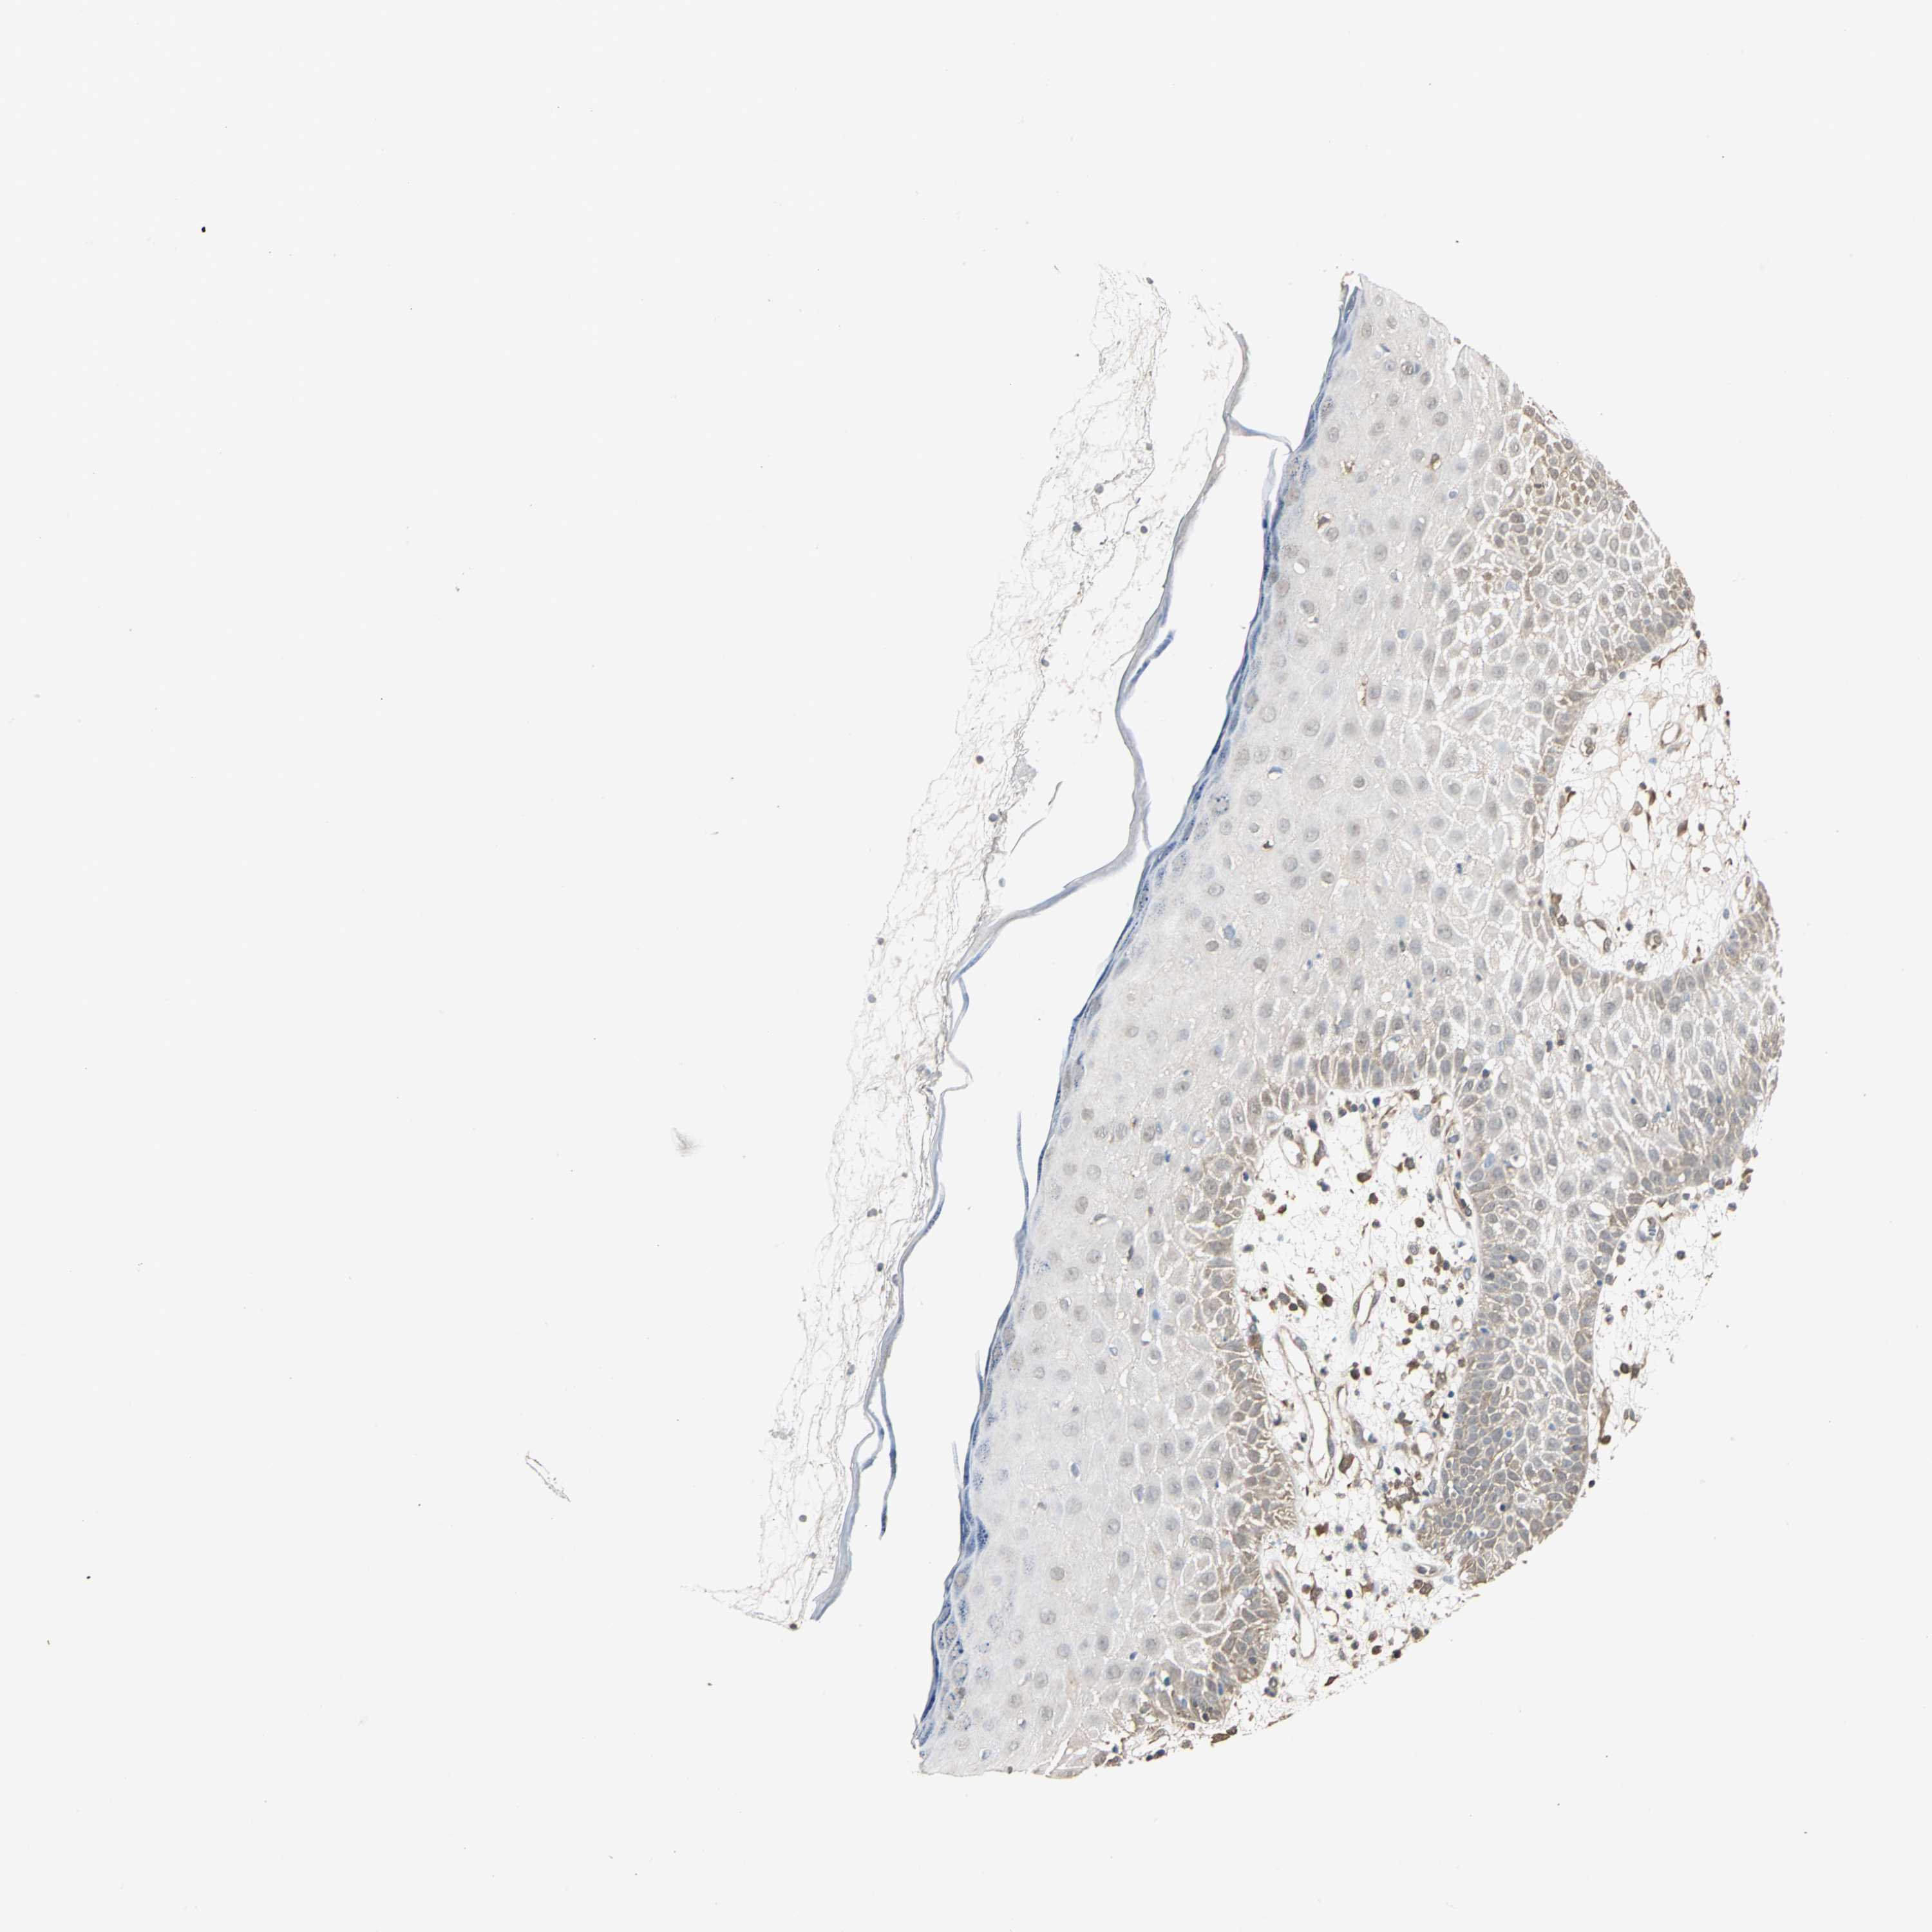

Basal cell and squamous cell cancer

SKIN CANCER - Protein expressioni

A mouse-over function shows sample information and annotation data. Click on an image to view it in a full screen mode. Samples can be filtered based on level of antibody staining by selecting one or several of the following categories: high, medium, low and not detected. The assay and annotation is described here.

Antibody stainingi

Antibody staining in the annotated cell types in the current human tissue is reported as not detected, low, medium, or high, based on conventional immunohistochemistry profiling in selected tissues. This score is based on the combination of the staining intensity and fraction of stained cells.

Each image is clickable and will lead to virtual microscopy that enables deeper exploration of all samples and also displays staining intensity scores, fraction scores and subcellular localization as well as patient and tissue information for each sample.

Antibody HPA004190

Antibody CAB005870

Squamous cell carcinoma, NOS

Basal cell carcinoma